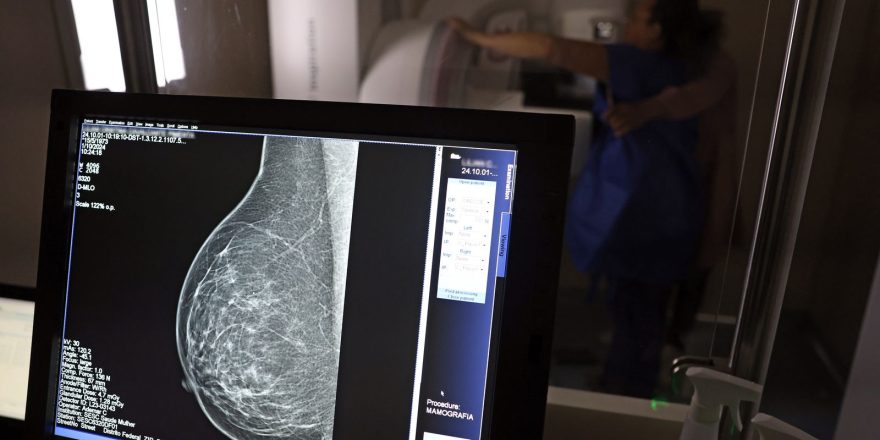

Data reforça a importância do diagnóstico precoce e do acesso ao tratamento para reduzir os impactos do câncer de mama no Brasil. @REPRODUÇÃO

Especialistas orientam que a atenção deve estar voltada a qualquer alteração nas mamas, como nódulos, mudanças no formato, secreções ou alterações na pele. O exame clínico, feito em consultas de rotina, e a mamografia continuam sendo as principais ferramentas para detectar o câncer ainda em estágios iniciais.